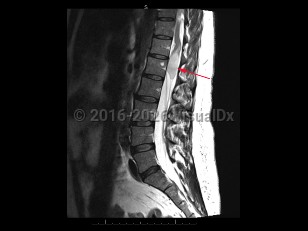

Cauda equina syndrome

Cauda equina syndrome is a neurologic emergency where damage to the lumbosacral plexus leads to loss of lower motor neuron function. Trauma, tumors or abscesses, large lumbar disk herniation, and spinal stenosis are some of the etiologies of this condition.

Onset is typically gradual but can be acute. Signs and symptoms include severe back pain that may radiate into one or both legs, saddle anesthesia, leg weakness or paraplegia, urinary or bowel dysfunction, sexual dysfunction, and gait disturbance. There may be reduced or absent patellar, Achilles, anal, and bulbocavernosus reflexes.